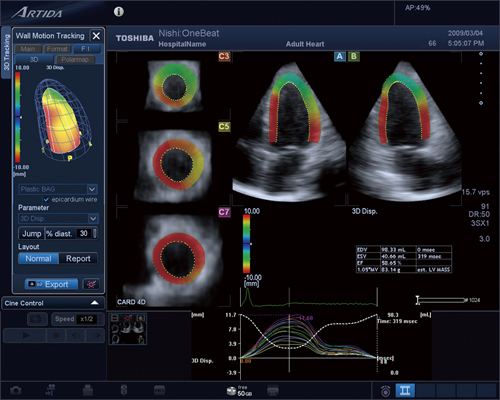

今回われわれは,リアルタイムの3D機能である4Dモードのデータでも,3D WMTが可能な“One-Beat 3D WMT”を開発した。One-Beat 3D WMTでは,4Dモードを用いているため,その名のとおり,1心拍のデータで心筋の3次元的な動きを解析することが可能である。4Dモードにより左室全体の3D画像を収集する場合,画質とフレームレートはFull 4Dに比べて低下することになる。そこでわれわれは,3D WMTのトラッキング設定を4Dモードの画像用に最適化し,One-Beat 3D WMTを実現した。健常例での解析結果を図5に示す。One-Beat 3D WMTは,従来の3D WMTの場合と同様にすべての機能を使用することが可能であり,3D WMTで実現したさまざまな解析を行うことができる。

図5 One-Beat 3D WMTの解析例(健常例)